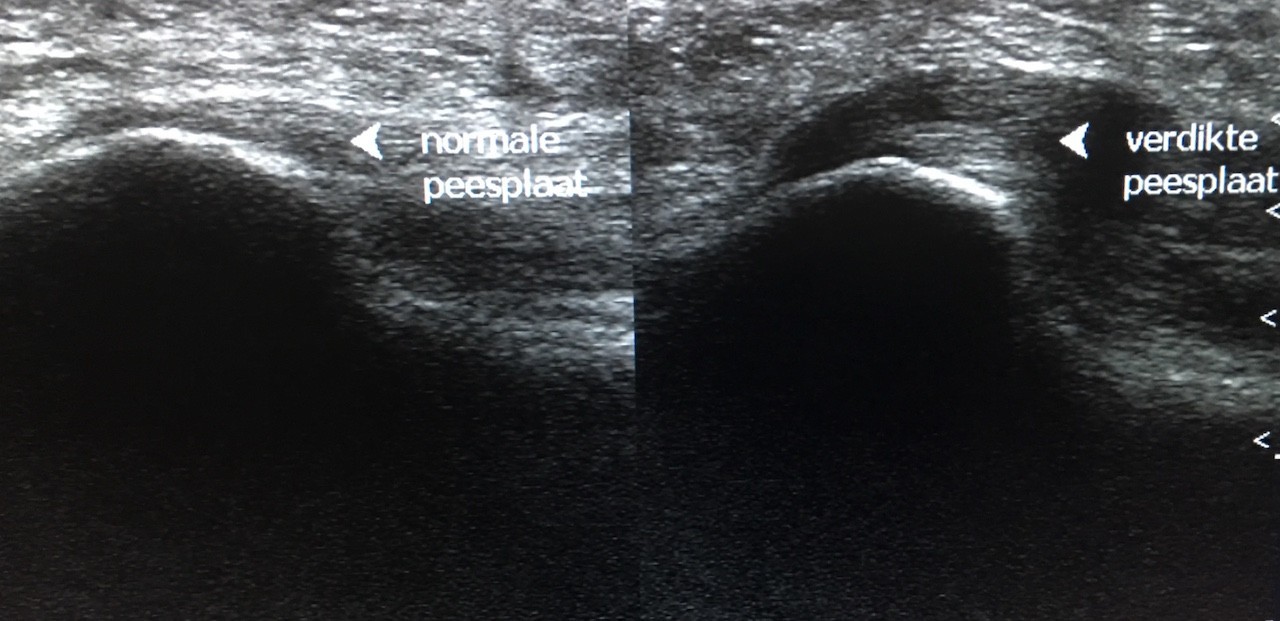

Sinds een jaar of tien geleden echografie zijn intrede deed binnen de fysiotherapie kon deze platte peesplaat zelf ook bekeken worden en al snel bleek dat het niet de hielspoor (het aangroeisel) maar de overbelaste en verdikte platte peesplaat was die de hielpijn veroorzaakte. Sommige zorgverleners zijn daar niet van op de hoogte en noemen de hielpijn nog altijd ‘hielspoor’, terwijl het in feite om een peesplaatontsteking (fasciitis plantaris) gaat.

Ja, in de meeste gevallen is het niet de hielspoor die hielpijn veroorzaakt, maar blijkt de pijn meestal afkomstig te zijn doordat de platte peesplaat (fascia plantaris) die aan de hiel vastzit overbelast raakt.